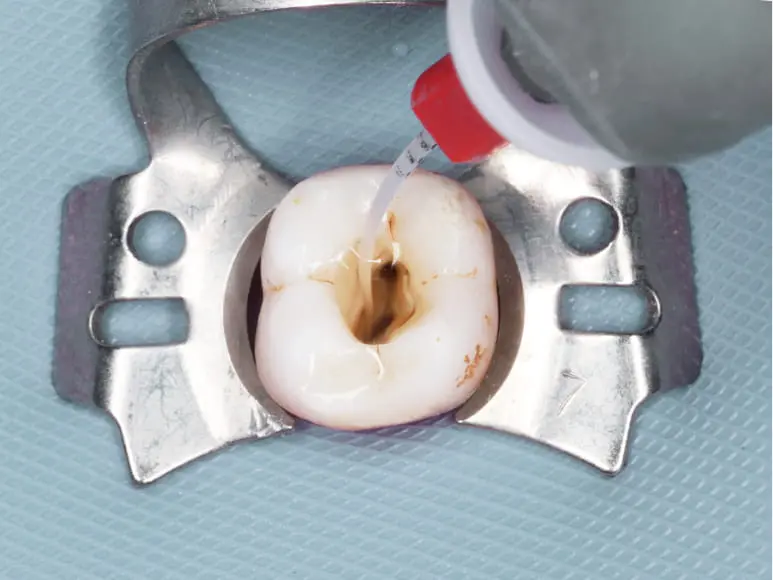

ラバーダムの準備

歯質がなくなったところから唾液が入らないように壁(隔壁)をつくり、ラバーダムがかけます。

洗浄・除菌

根管の内部を専用の薬液で洗浄・消毒します。

薬剤の充填

MTAセメントを根管内に詰めて封鎖し、術後の細菌侵入・増殖を抑制します。